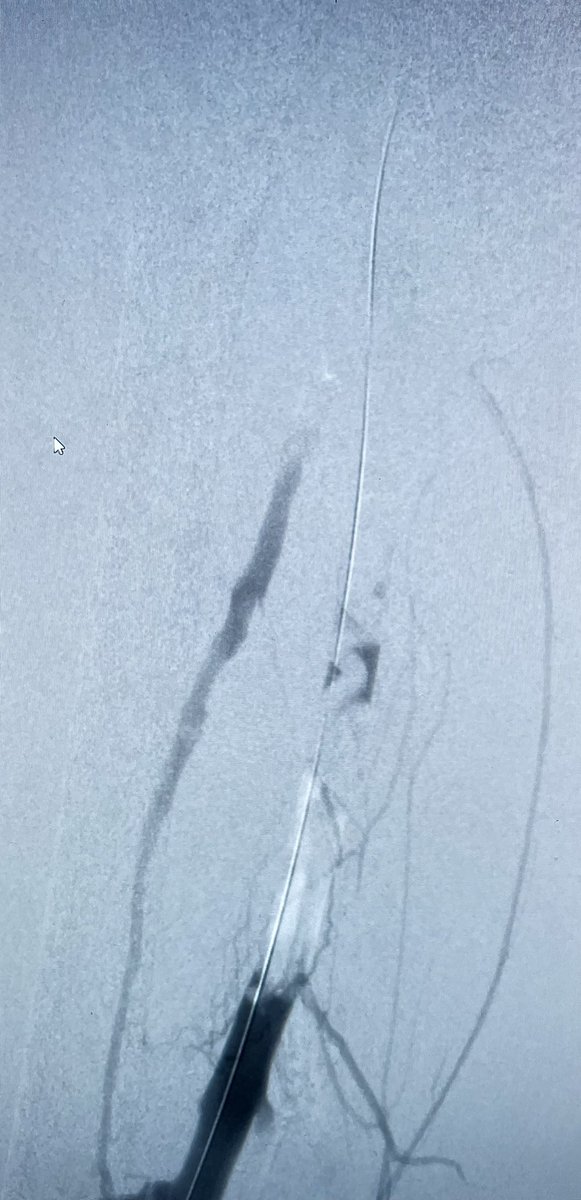

@ArmoghanMD

Acute limb ischemia in 89 years old female with H/O afib not on anticoagulation due to recent GI bleed. Unable to use tpa due to age and GI bleeding. Treated with thrombectomy using angiojet and balloon angioplasty